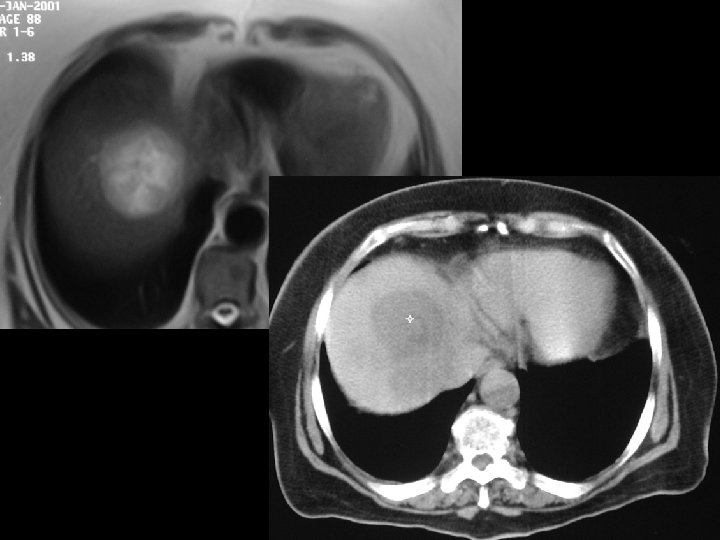

RF (Radyofrekans Tümoral Ablasyon) üBilgisayarlı tomografi veya US kılavuzluğunda üÖzellikle karaciğerdeki 3 cm metastatik veya primer neoplazilerin üRF iğnesi ile radyofrekans dalgaları verilerek oluşturulan moleküler ısı sonucu tümoral lezyonun ablasyonu